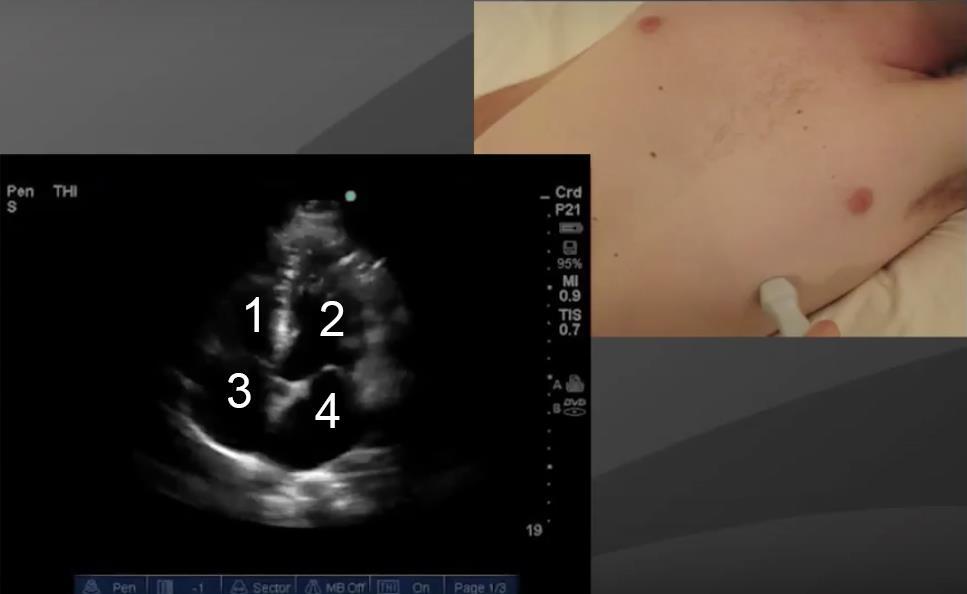

Cardíaco: Vista apical de 4 cámaras - Imagen

1. Ventrículo derecho (VD)

2. Ventrículo izquierdo (VI)

3. Aurícula derecha (AD)

4. Aurícula izquierda (AI)